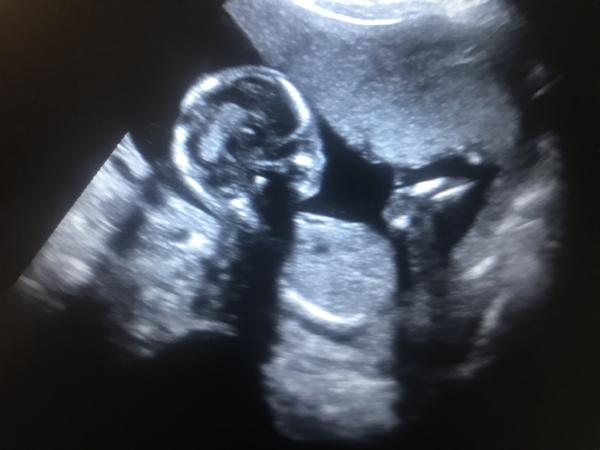

Shoj holky jen me zajima doktor dnes nerekl na utz nic jsem 16+4tt pohlavi rekne az 20tt kamaradce jsem poslala fotku ze srandy ze mame buchtu a odepsala ze ji tam opravdu vidi myslite si ze je to mozne ?

To velike je steheni kost ale zakrouzkováa jsem 3 carky ktere si mysli ze je buchta 😂